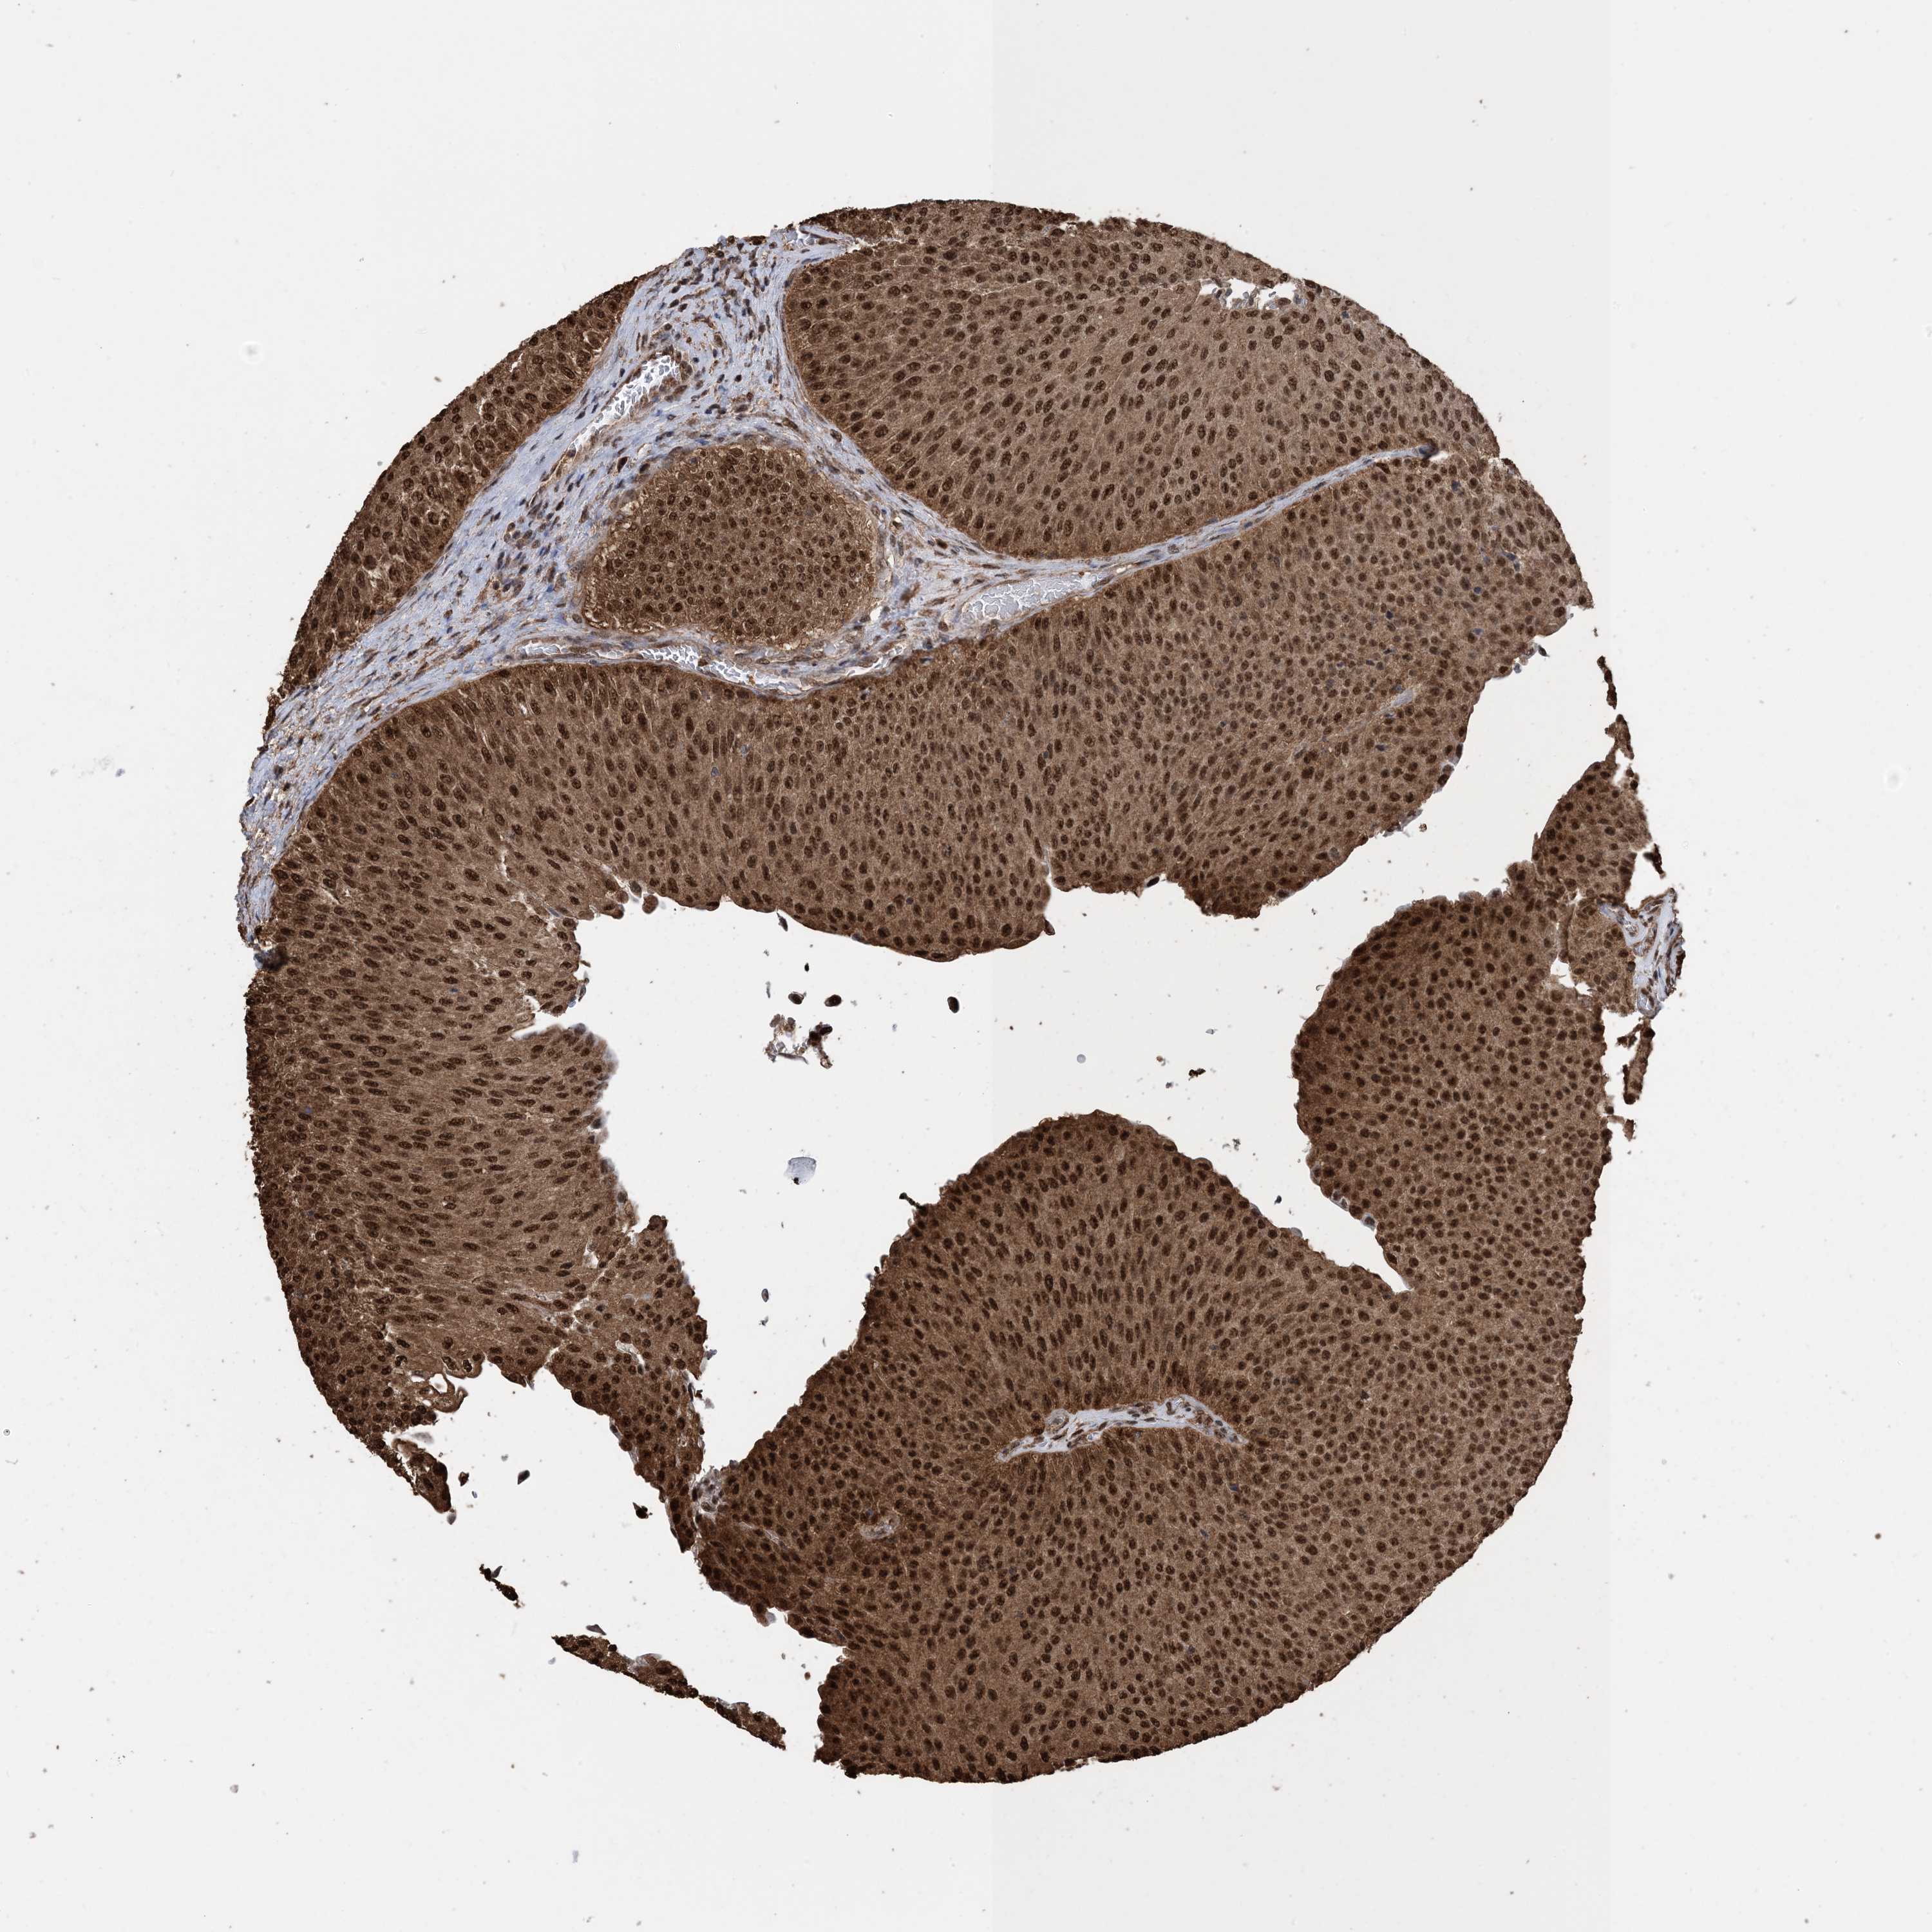

UROTHELIAL CANCER - Protein expressioni

A mouse-over function shows sample information and annotation data. Click on an image to view it in a full screen mode. Samples can be filtered based on level of antibody staining by selecting one or several of the following categories: high, medium, low and not detected. The assay and annotation is described here.

Note that samples used for immunohistochemistry by the Human Protein Atlas do not correspond to samples in the TCGA dataset.

Antibody stainingi

Antibody staining in the annotated cell types in the current human tissue is reported as not detected, low, medium, or high, based on conventional immunohistochemistry profiling in selected tissues. This score is based on the combination of the staining intensity and fraction of stained cells.

Each image is clickable and will lead to virtual microscopy that enables deeper exploration of all samples and also displays staining intensity scores, fraction scores and subcellular localization as well as patient and tissue information for each sample.

Antibody HPA052504

Antibody CAB017451

Antibody CAB032815

Staining

High

Medium

Low

Not detected

Intensity

Strong

Moderate

Weak

Negative

Quantity

>75%

75%-25%

<25%

None

Location

Nuclear

Cytoplasmic/membranous

Cytoplasmic/membranous,nuclear

Urothelial carcinoma, High grade

Urothelial carcinoma, NOS

Urothelial carcinoma, Low grade